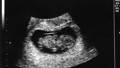

A baby boy has been born following a new fertility treatment that awakens dormant eggs in women who have stopped menstruating.The treatment could help women who have left child-bearing too late, or have been left infertile after treatment for cancer. But some have raised concerns that the technique has been rushed to the clinic before being properly tested.

Women are born with millions of immature eggs, or follicles, but only around 400 mature to the point where an egg is released into the fallopian tubes and could be fertilised. But some of these follicles remain, even after a woman has stopped menstruating.Now researchers have found a way to wake these dormant follicles and produce eggs that are capable of being fertilised. The first test of this technique has resulted in a baby boy, born in December 2012 in Japan.